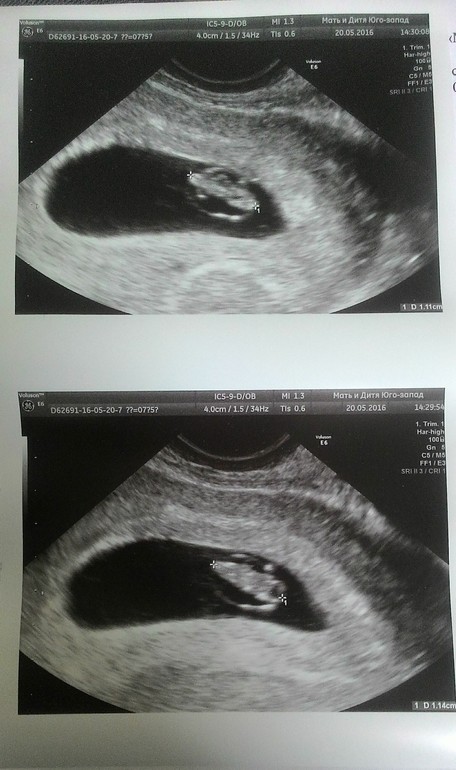

назначили еще анализы, все в норме, но прогик немного упал, со 101 до 74,5....сегодня была у врача, сказала, что все ок, но на всякий случай послушали сердечко.

СБ+, КТР- 11мм ( 7 НЕД)

По месячным у нас 7 нед. и 5 дней, но овуляция была поздняя, не 9 апреля, а с 12 на 13.

Вот такая эволюция моей маленькой точки!!!!